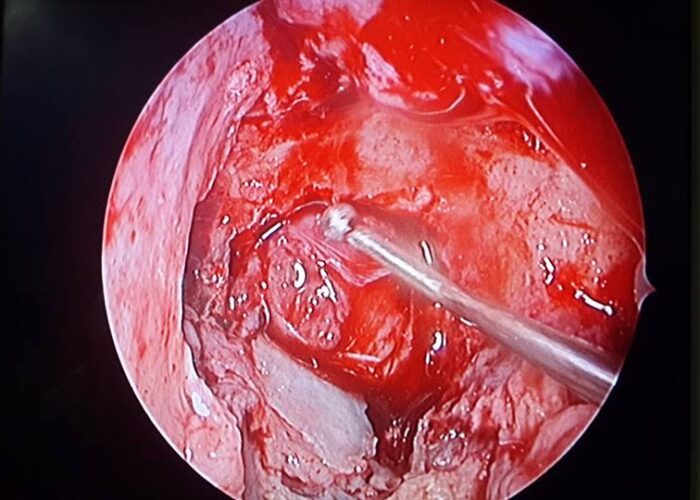

3 Endoscopic Pituitary Cases in Manik Hospital